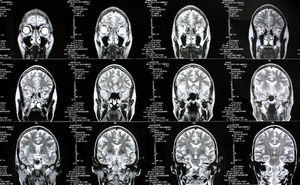

Gehirn-Scans: Resveratrol wirkt gegen Alzheimer (Foto: pixelio.de, Rike) |